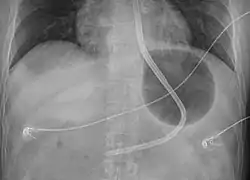

| Steps | 1) Intubate 2) Verify balloons intact 3) Place tube via the mouth 4) Verify placement by X-ray 5) Inflate stomach balloon 6) Apply traction 7) Inflate the esophageal balloon if needed[1] |

Preparation involves intubation followed by placing the person on their back at 45 degrees.[1] The device is than checked to make sure no leaks are present.[1] It is than placed via the mouth and 50 ml of air are added to the stomach balloon.[1] An X-ray is than done to verify placement and once confirmed more air is added.[1] Traction can than be applied.[1] Bleeding is than checked for, and if present the esophageal balloon may be inflated using a manometer.[1]

- Verify that the end of the tube is in the stomach by X-ray